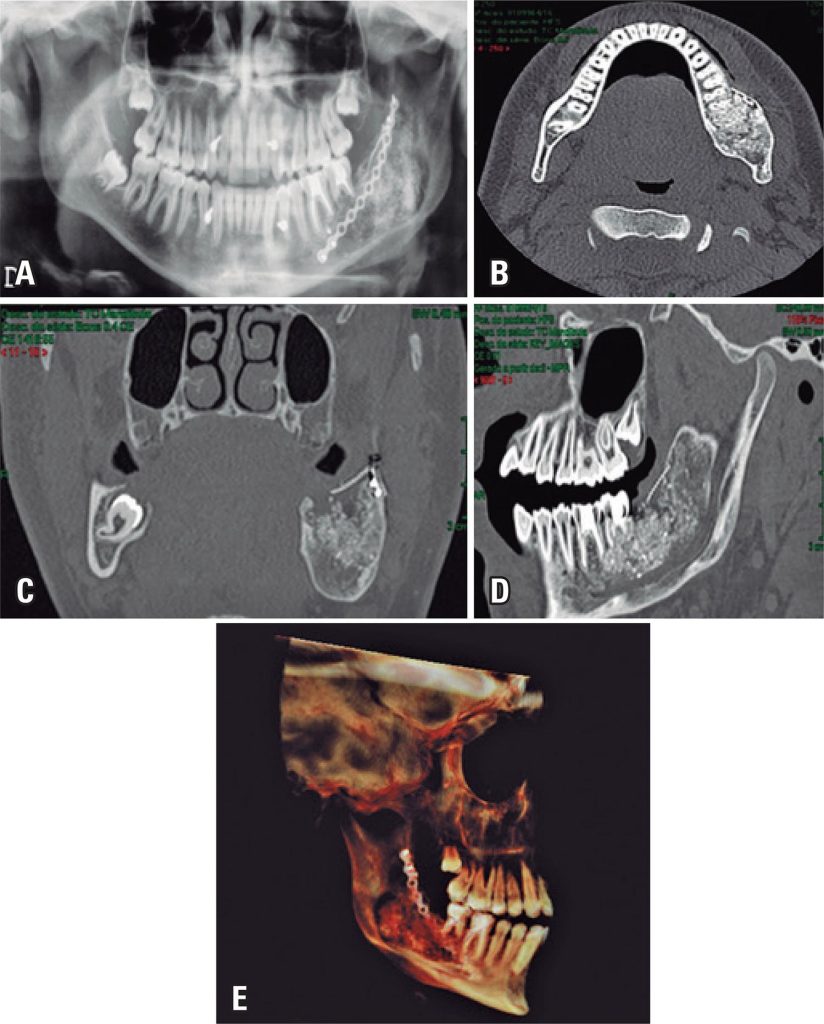

Utilização off-label das rhBMP-2 como estratégia de regeneração do tecido ósseo em ameloblastoma mandibular

A reconstrução óssea dos maxilares após ressecções tumorais é uma das tarefas mais difíceis para o cirurgião maxilofacial. As propriedades osteogênicas, osteoindutoras, osteocondutoras e não antigênicas do osso autógeno o colocam como o padrão-ouro para a solução de problemas de disponibilidade óssea. Entretanto a coleta do enxerto ósseo necessita de um segundo sítio cirúrgico, aumentando significativamente o custo e a morbidade associados ao procedimento reconstrutivo. A enxertia óssea ganhou uma excelente ferramenta com a descoberta das proteínas ósseas morfogenéticas na década de 1960. O benefício da obtenção de matriz óssea verdadeira e funcional, sem a necessidade de um segundo sítio cirúrgico, parece ser a grande vantagem do uso das proteínas ósseas morfogenéticas. Neste contexto, o objetivo deste estudo foi analisar a utilização da rhBMP-2 na regeneração óssea de ameloblastoma mandibular unicístico, detalhando sua estrutura, seus mecanismos de sinalização celular e sua eficácia biológica, além de apresentar potenciais vantagens e desvantagens da utilização clínica das rhBMP-2, enquanto estratégia regenerativa.